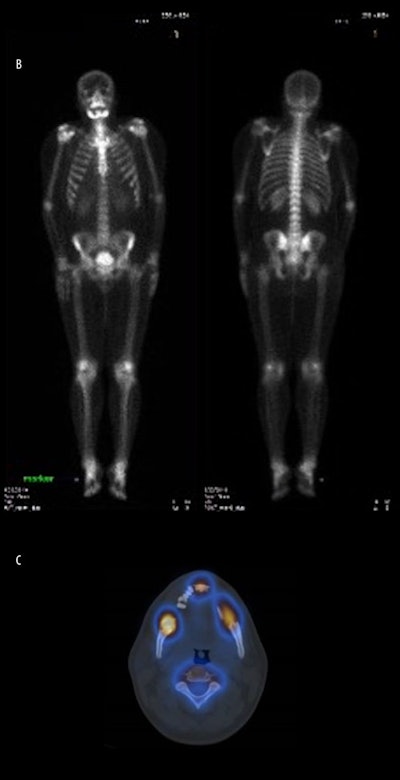

A computed tomography (CT) scan showed multiple nonexpansible osteolytic lesions associated with multiple floating teeth on the right anterior upper jaw and bilaterally on the lower jaw. A whole-body CT scan showed increased uptake in both mandibular bodies, extending to the angle of the mandible. A single photon-emission CT (SPECT/CT) scan showed intense localized osseous uptake in the same areas noted on the whole-body scan, the authors wrote.

(A) Multidetector CT axial view slices of the maxilla and mandible reveal nonexpansible osteolytic lesions in the upper and lower jaws. (B) Whole-body bone CT shows increased uptake in the mandible. (C) SPECT/CT shows a high rate of metabolic activity in the same regions.